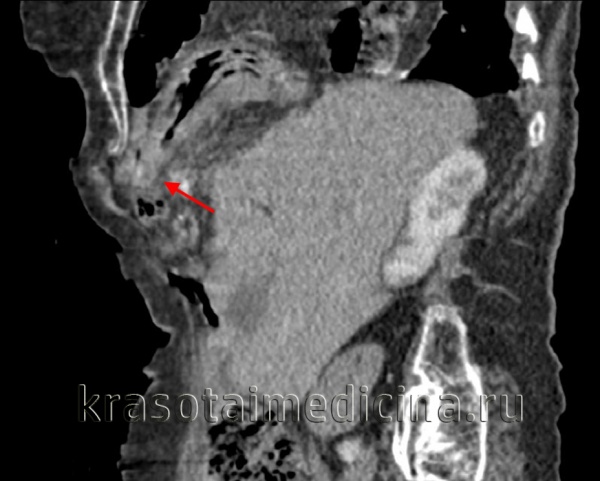

(Слева) На рентгенограмме грудной клетки у подростка, пострадавшего в ДТП, определяется пневмоторакс, плевральный дренаж и назогастральный зонд в виде извитой тени в проекции грудной клетки.

(Справа) На аксиальной КТ у этого же пациента определяются характерные признаки повреждения диафрагмы, в т.ч. симптом «выпадения» внутренних органов. Желудок находится в грудной клетке. Обратите внимание, что он прилежит к задним медиальным отделам грудной стенки. Желудок выглядит сдавленным в месте прохождения через дефект в диафрагме (симптом «воротника»). (Слева) На аксиальной КТ с контрастным усилением визуализируется желудок, находящийся в грудной клетке, выпавший через дефект в диафрагме. Желудок прилежит к задним медиальным отделам грудной стенки. Передняя стенка желудка, не ограниченная диафрагмой, напрямую соприкасается с легким.

(Справа) На корональной КТ у этого же пациента визуализируется желудок, выбухающий кверху сквозь дефектный участок в диафрагме.